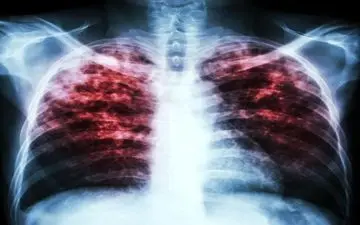

رژیم غذایی سالم میتواند عفونتهای ناشی از بیماری سل را تا ۵۰ درصد کاهش دهد.

محققان بیمارستان عمومی ماساچوست در مطالعهای کوچک نشان دادند که یک واکسن ۱۰۰ساله که بهطور گسترده برای پیشگیری از سل…

قرار است بررسی واکسن سل به عنوان یک راه حل برای مقابله با ویروس کرونا در سطح بینالمللی گسترش یابد.

تحقیق جدید نشان می دهد واکسن جدید بیماری سل به کاهش ریسک بیماری آلزایمر کمک می کند.

فوق تخصص آسم، آلرژی و ایمونولوژی بالینی گفت: نوزادان در بدو تولد طبق روال چندین ساله واکسن های 'ب ث ژ' (سل) و فلج…